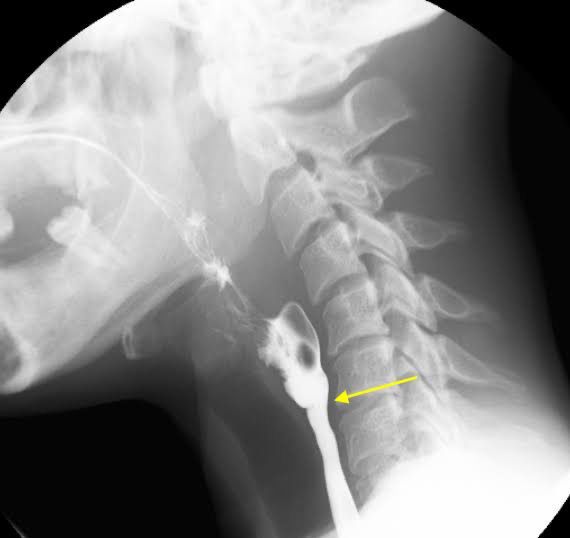

Plummer-Vinson syndrome is a condition found in people suffering from iron deficiency anemia for a prolonged period of time. It is more common in women and presents with dysphagia, atrophic glossitis, angular somatitis and esophageal webs. Treatment is done by treating the iron deficiency anemia, with the help of iron supplements. Picture above bows esophageal webs that helps in diagnosing Plummer-Vinson syndrome. Picture credit: https://www.cureus.com/articles/24080-a-rare-case-of-plummer-vinson-syndrome